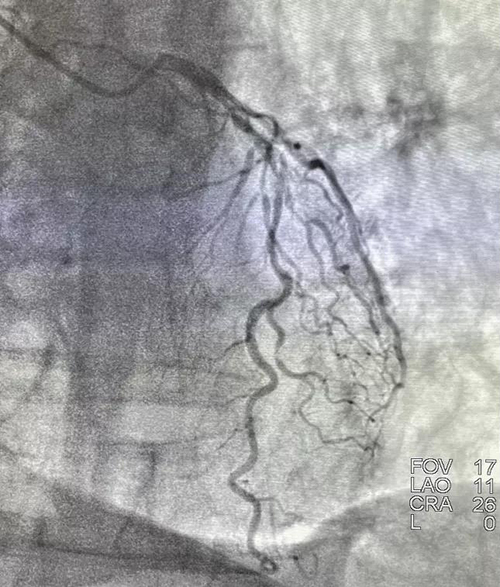

1月8日,山东第一医科大学附属省立医院(山东省立医院)心内科成功为一例严重冠脉钙化病变患者进行了准分子激光斑块消蚀术(ELCA),并顺利植入冠脉支架,腔内影像显示支架膨胀贴壁良好,未见夹层血栓。

术前